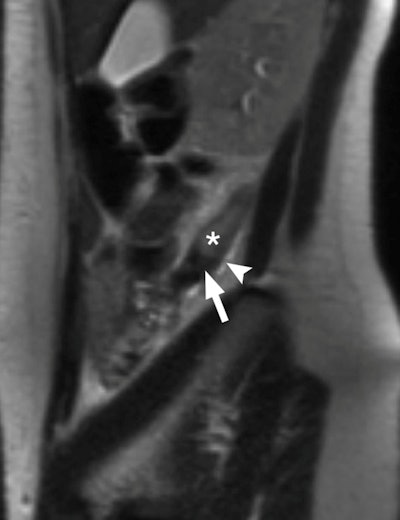

| True-positive MRI of a 24-year-old pregnant woman with surgically proved appendicitis. Sagittal T2-weighted single-shot fast spin-echo through appendix (*) shows dilated appendix that measures up to 12 mm. High-signal-intensity fluid and edema (arrowhead) are present around the appendix. Low signal intensity within the lumen toward the base of the appendix (arrow) may represent an appendicolith. Image courtesy of Radiology. |